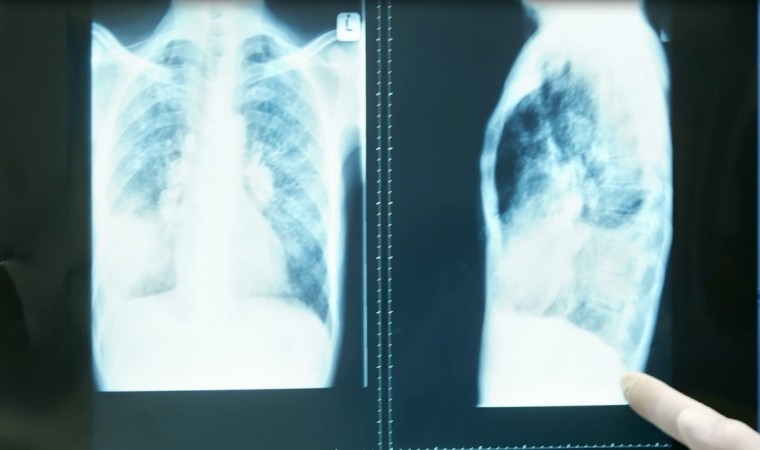

KOAH’ın öksürük, balgam ve nefes darlığı gibi kalıcı semptomlarla seyreden, önlenebilir ve tedavi edilebilir bir hastalık olduğunu belirten Uzm. Dr. Şule Yıldız, bu hastalığın ileri yaşlarda daha sık görüldüğünü ancak genç yaşlarda da ortaya çıkabileceğini ifade etti. Yapılan araştırmalara göre her 10 yetişkinden birinin KOAH hastası olduğunu söyleyen Dr. Yıldız, “KOAH’ta yetersiz tanı önemli bir sorundur. Hastaların yüzde 60 ila 85’i halen tanı almamış durumdadır. İç ve dış ortamda odun, kömür, tezek gibi yakıtların dumanlarının solunması da KOAH’a sebep olmaktadır. Bunun yanında yetersiz beslenme ve çocuklukta geçirilen akciğer enfeksiyonları da hastalığa zemin hazırlayabilmektedir” ifadelerini kullandı.

Hastalığın tanısında nefes ölçüm testi uygulandığını belirten Uzm. Dr. Yıldız, şu bilgileri paylaştı:

“Solunum fonksiyon testi olarak isimlendirilen bu test, solunum yolundaki darlığı ve hava akımındaki azalmayı tespit etmektedir. KOAH’ın bireysel tedavisinde inhaler dediğimiz nefes açıcı ilaçlar kullanılmaktadır. Bu ilaçlar, hastanın nefes darlığını azaltmayı ve yaşam kalitesini artırmayı hedefler. Ayrıca hastalığın seyrini değiştirecek alevlenmelerden ve zatürreden korunmak için grip ve zatürre aşılarının yapılması gerekmektedir.”